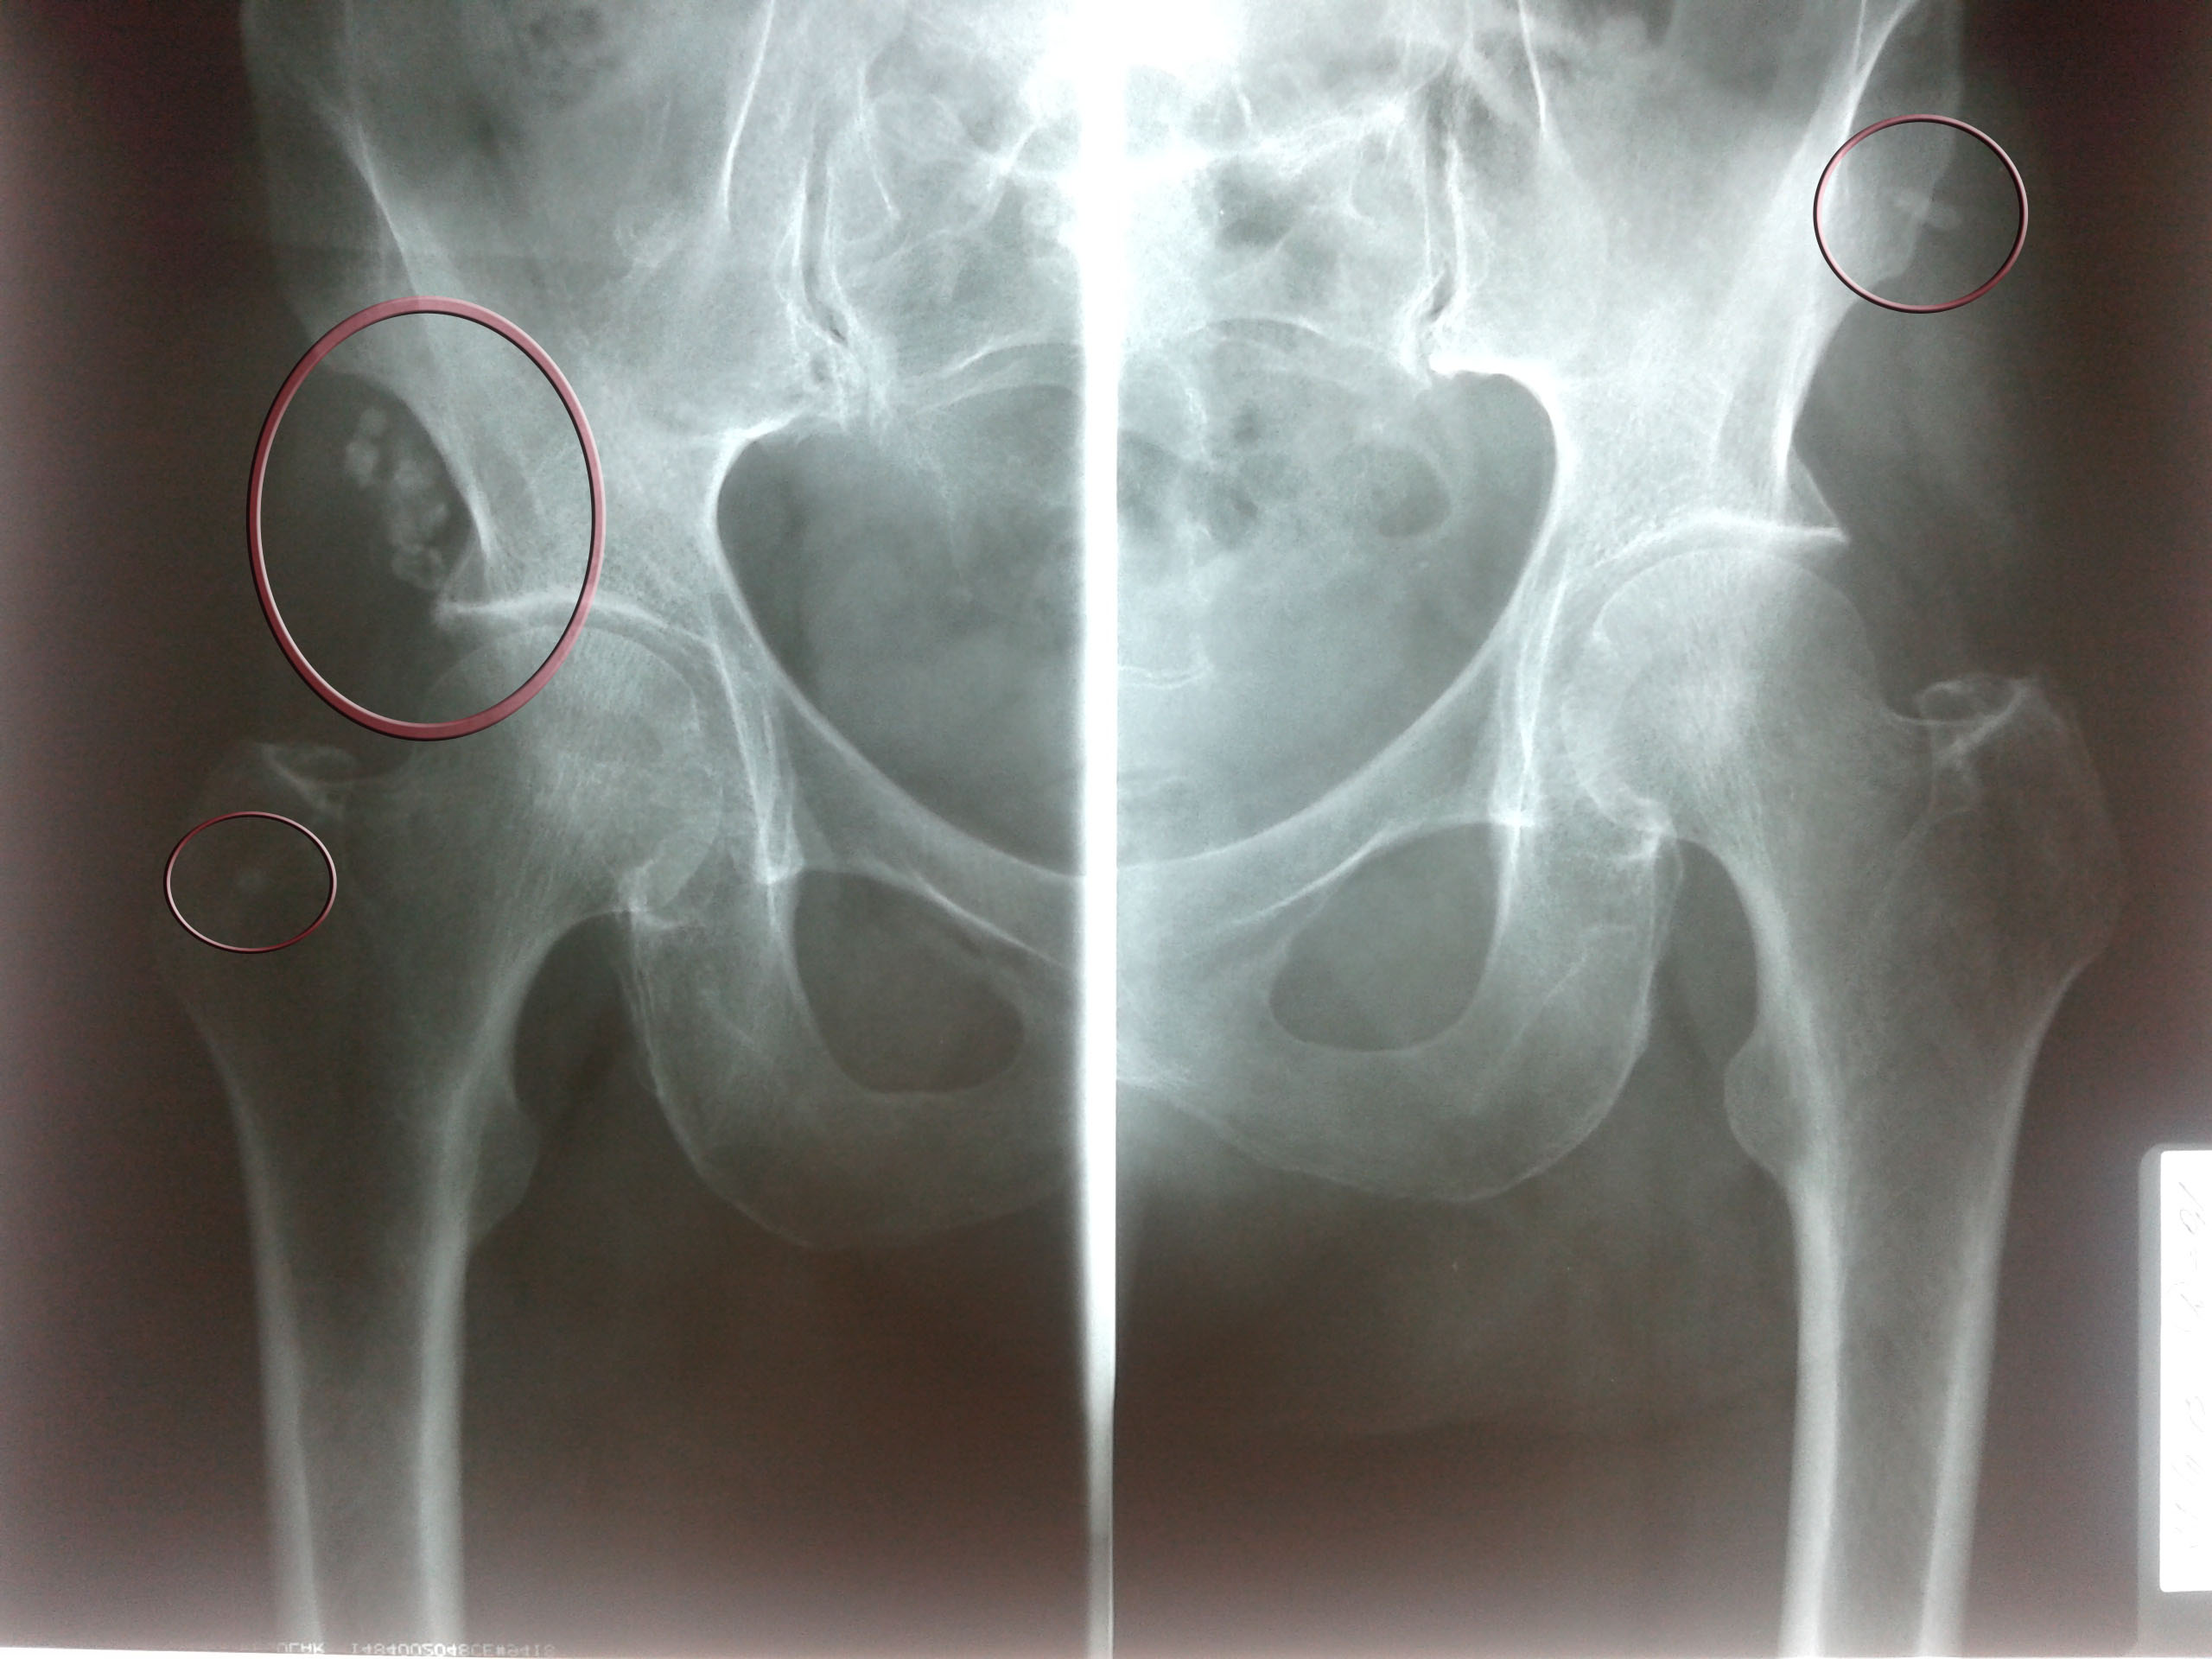

Рентгеновские снимки: Синовит тазобедренного сустава